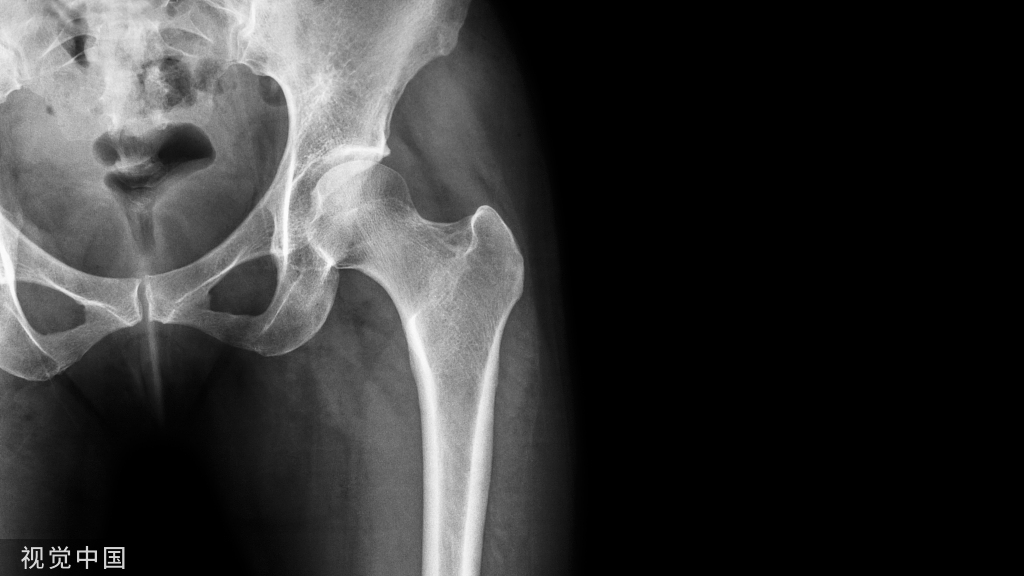

这是在X线片可以更好地观察(黄箭头 )。